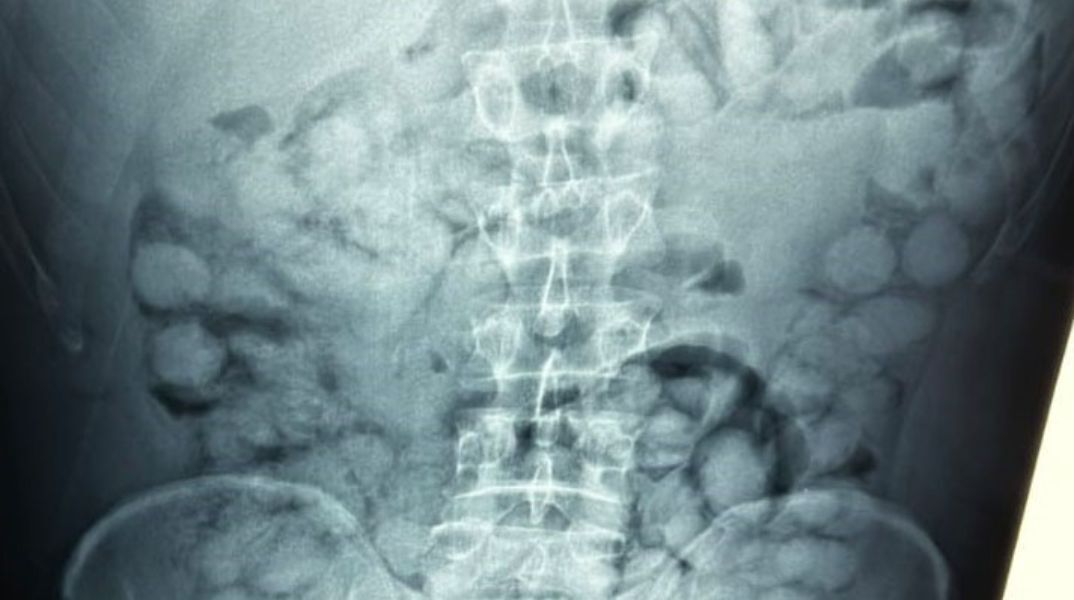

Ο άνδρας που ταξίδευε από Βραζιλία μέσω Γαλλίας, είχε καταπιεί 100 συσκευασίες κοκαΐνης. Η κάθε συσκευασία ήταν 10 γραμμαρίων και καθαρότητας 90%.